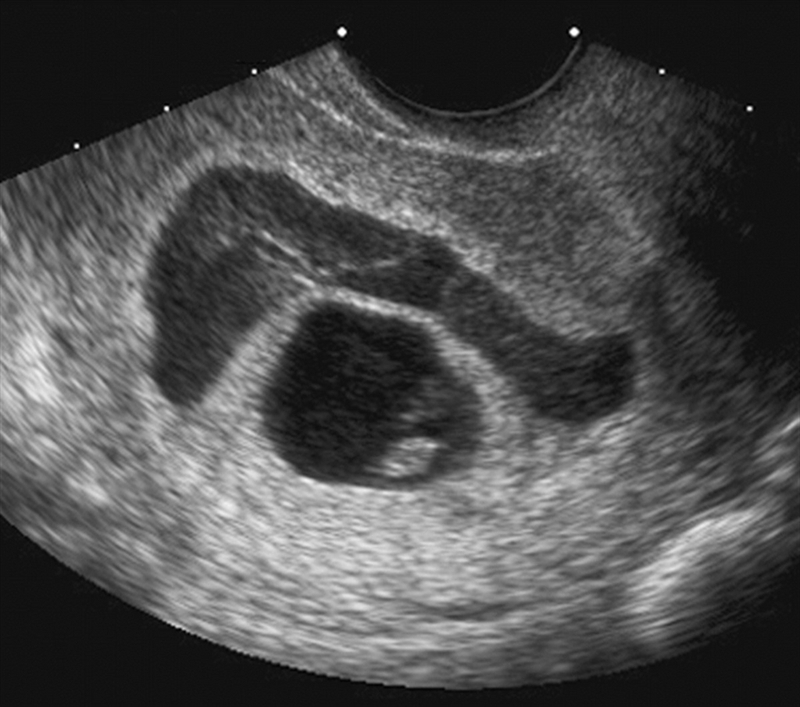

Sự thay đổi bất thường về màu sắc ở khí hư âm đạo luôn là vấn đề khiến các chị em phụ nữ cảm thấy lo ngại về mặt sức khỏe cũng như chức năng sinh sản ở bản thân. Đặc biệt đối với các mẹ bầu, hiện tượng ra dịch nâu khi mang thai 7 tuần tuổi càng là vấn đề nghiêm trọng, đáng được quan tâm.

Theo chia sẻ của nhiều bác sĩ chuyên khoa, tình trạng ra dịch nâu khi mang thai 7 tuần có thể đến từ các nguyên nhân sinh lý bình thường. Tuy nhiên, cũng không loại trừ khả năng đó là một trong những dấu hiệu cảnh báo về những biến chứng nguy hiểm khác.